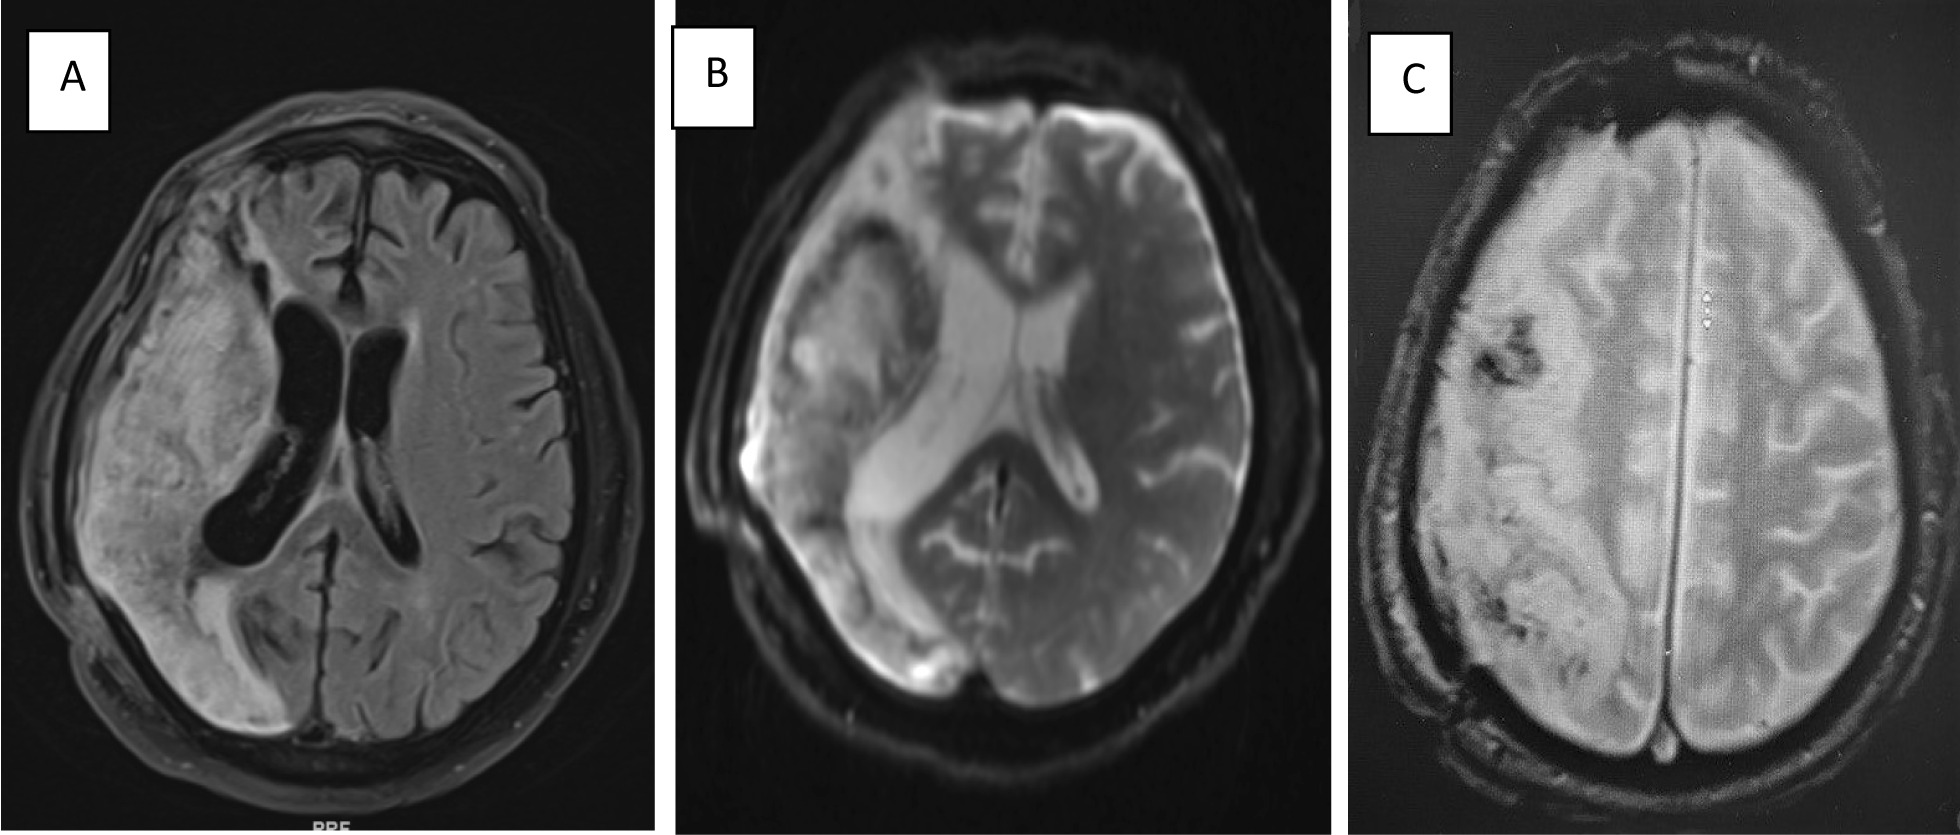

Fig. 2.

A Axial section of brain MRI Fluid-Attenuated Inversion Recovery (FLAIR) image showing subacute infarction extensively affecting the right temporal area. B Lesion in the T2-weighted MRI image. C Gradient echo showing blooming artifacts representing hemorrhagic transformation

Anatomically, KBS is frequently due to lesions affecting bilateral temporal lobes. In addition, the hippocampus, uncus, cingulate gyrus, and amygdala play a significant role in the pathogenesis of KBS. Moreover, a disturbance of the pathways that provide the neurological connections of the limbic system, medial thalami, and frontal lobe is accountable for impaired memory and emotions, which also contribute to the development of KBS [23, 24]. In other cases, KBS symptoms were found after unilateral brain lesions, such as right subdural hematoma, infarction, or lobectomy of the left temporal lobe. In previous published studies, this syndrome is a consequence of visual input interruption to the limbic system as described by Geschwind [25]. Müller et al. mentioned that KBS seems to follow an obliteration of the thalamus, frontal cortex, and limbic system pathway connections [17], and Hreniuc et al. stated that their patient has disruption in the right temporal lobe and amygdala. However, in our case, the patient has a lesion in the temporal area of the nondominant hemisphere; this has been reported by Hreniuc et al. in their patient [10]. Since a disturbance in the level of consciousness at the time of recovery might account for the manifestations of KBS, the CT scan is a distinguishing imaging test for patients who suffer brain injuries. Additionally, for those who present with neurobehavioral symptoms, MRI is necessary to structurally visualize brain lesions [23, 26]. The clinical manifestations of this syndrome may appear in patients without morphological changes in the brain CT scan, particularly the temporal lobes. For this reason, brain evaluation by MRI scan should be considered in patients with cerebral insults.